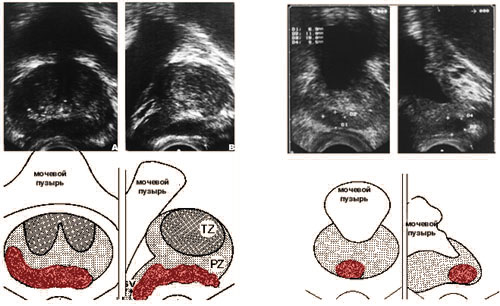

Трансректальная ультразвуковая томография.

Опухоль предстательной железы.

Техника брахитерапии основана на одной или нескольких модификациях закрытого чрезпромежностного доступа, который первоначально был описан Holm и соавторами в 1983 г. Такой подход позволяет проводить имплантацию постоянного источника в амбулаторных условиях. Большинство методик включают УЗ изображение в режиме реального времени или флюороскопию, которые обеспечивают прямую визуализацию положения игл в простате и их координацию на шаблоне.

После спинномозговой или общей анестезии пациент располагается в положении на спине (как для литотомии), УЗ датчик вводится в прямую кишку и фиксируется. Затем устанавливается и фиксируется промежностный шаблон для введения игл. Заправленные источниками иглы вводятся через соответствующие отверстия шаблона согласно предварительному планированию.

Промежностные шаблоны обычно представляют собой жесткую матрицу с определенным расположением отверстий. Шаблон крепится к УЗ датчику, который может быть продвинут вперед или назад для визуализации положения троакаров. Современная ультрасонография позволяет визуализировать как поперечные так и продольные срезы, что позволяет точно разместить иглы. Предстательная железа удивительно подвижный и эластичный орган, и процесс введения игл может привести к ее движению или смещению. В результате окончательное положение зерен может оказаться неточным. Таким образом, мониторинг процесса имплантации позволяет оператору выявить неправильное расположение и переместить зерна.